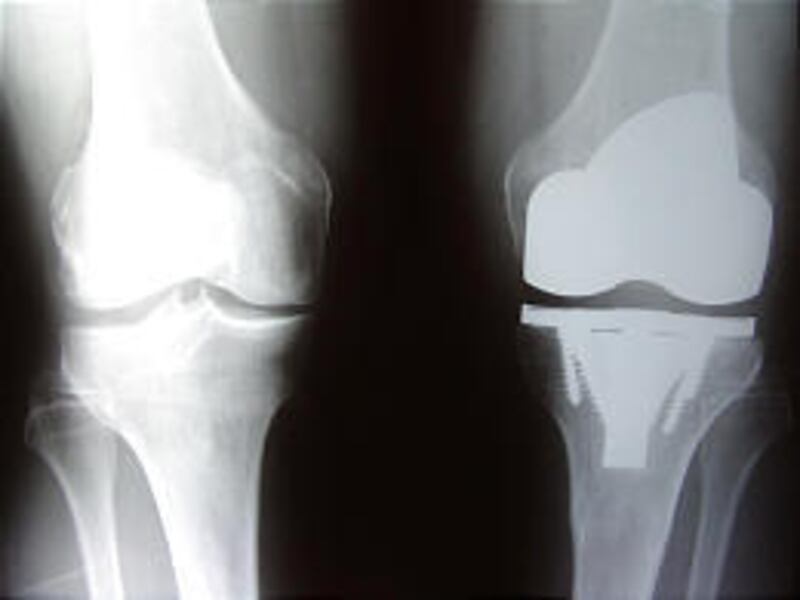

Two years ago this month, Rasmussen implanted Wright Medical's ADVANCE Medial-Pivot Total Knee System, which has three parts: a titanium platform with a stem that goes into the lower bone, a cap made of cobalt chromium metal that goes over the curve of the femur's end and a polyethylene plastic liner that sits on the platform.

Because of the material used, the new knee is subject to osseointegration, which means Hancock's bone will grow up and through it, becoming part of it. As for fixing it, a stem with four fins for rotational stability goes down into the bone. There are four spikes around the outside and four titanium screws, Rasmussen says.